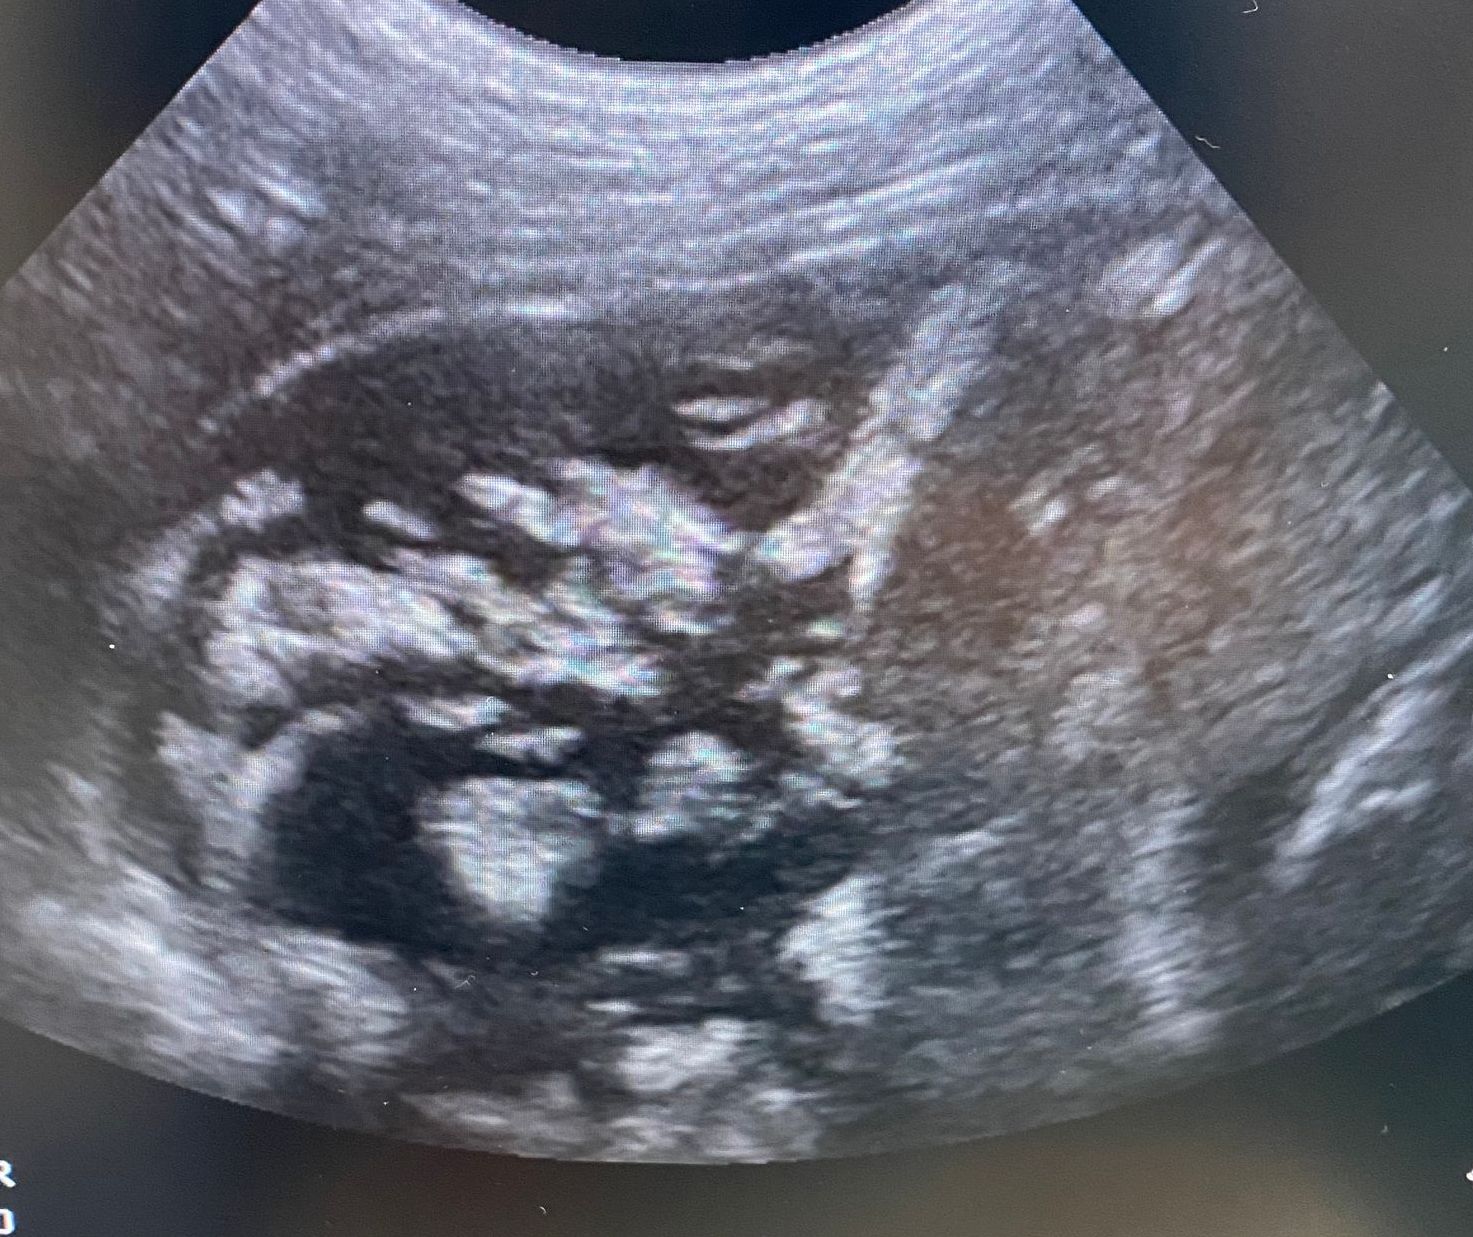

- Echocardiographie

Cet examen permet notamment de déterminer l'origine d'un souffle détecté au cours d’une consultation. Il permet aussi d’apprécier les répercussions sur le fonctionnement du cœur.

Selon les résultats de l’examen, un traitement est mis ou non en place. Il diffère en fonction des maladies et des stades d’évolution de celle-ci. Pour plus de renseignements, vous pouvez consulter la page cardiologie.